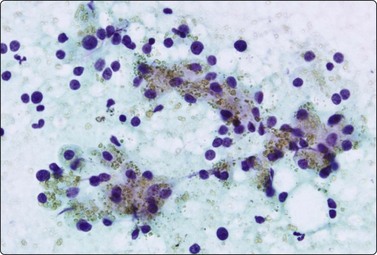

Myeloid metaplasia (Fig. 10.34)

The findings in myeloid metaplasia include normoblasts, myelocytes and megakaryocytes intermingled with the cells of normal splenic tissue. Normoblasts are easily recognized by their relatively small, round, hyperchromatic nuclei and their homogeneous, dense eosinophilic or amphophilic cytoplasm. Megakaryocytes may be mistaken for malignant neoplastic cells but should be recognizable by the giant, lobulated nucleus and the abundant, granular cytoplasm. Myelocytes have specific cytoplasmic granules. All these features are best seen in MGG-stained smears.234

image

(A) Megakaryocyte and several erythroblasts adjacent to smeared lymphoid cells (MGG, HP); (B) Erythroblasts, myelocytes, lymphoid cells (MGG, HP).